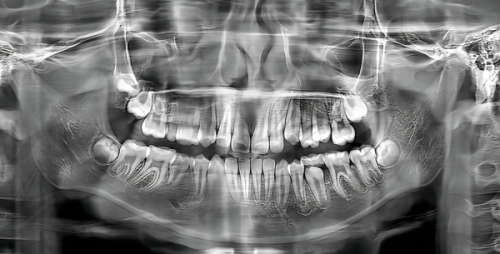

种植牙是合肥新安口腔医院的主要项目之一,包括单颗种植牙手术、多颗种植牙手术、半口牙种植、全口牙种植等。单颗种植牙手术是选择合适的点位和种植体对牙槽骨进行填充,填充结束后再做一次亚冠的修复治疗,更终对牙齿进行整体的清理和消毒,确保没有杂菌感染即可完成手术。单牙种植的原理一般是通过手术将人工牙根植入牙齿掉落的牙龈位置,人工牙根和患者本身的牙槽骨融合后,在牙根上安装金属烤瓷冠,具有类似牙齿根部的功能,几乎与天然牙齿一样坚固美观。

单颗牙种植成效通常比较理想,手术后一般可以补上牙齿缺失的牙体缺损问题,但每个患者的实际情况不同,选择的医院不同,手术成效也会有所差异。单颗牙种植的价格一般为5000 - 30000元,价格影响因素与患者选择的种植牙材料有直接关系,质量越好的种植牙材料,费用自然会贵一些。